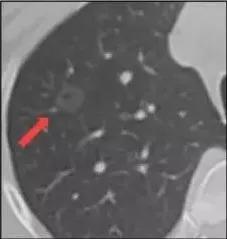

2.磨玻璃结节

结节长相:肺内密度轻微增加,增加程度小于实性改变,呈模糊的云雾状,并可见其内血管和支气管纹理。

产生原因:根据肺部磨玻璃影内部成分均一程度的不同,磨玻璃结节又可分为单纯磨玻璃结节及混合型磨玻璃结节。造成磨玻璃结节的原因包括感染性病变、肿瘤等多方面。